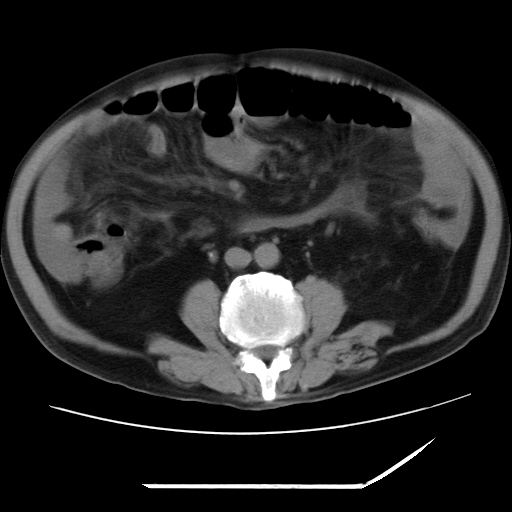

以下是引用zxl51642在2009-8-12 18:55:00的发言:[br]1、肠系膜脂肪浑浊,密度增高,腹水,支持腹膜炎诊断;2、右肾盂及输尿管中段结石,左输尿管起始段结石;3、胆囊切除术后改变?4、双侧胸膜腔少量积液;5、胰腺体积不大,勾勒清楚,肾前筋膜无增厚,不支持胰腺炎,请结合血尿淀粉酶及临床。

以下是引用黑白光影在2009-8-12 22:06:00的发言:[br][quote]以下是引用zxl51642在2009-8-12 18:55:00的发言:[br]1、肠系膜脂肪浑浊,密度增高,腹水,支持腹膜炎诊断;2、右肾盂及输尿管中段结石,左输尿管起始段结石;3、胆囊切除术后改变?4、双侧胸膜腔少量积液;5、胰腺体积不大,勾勒清楚,肾前筋膜无增厚,不支持胰腺炎,请结合血尿淀粉酶及临床。